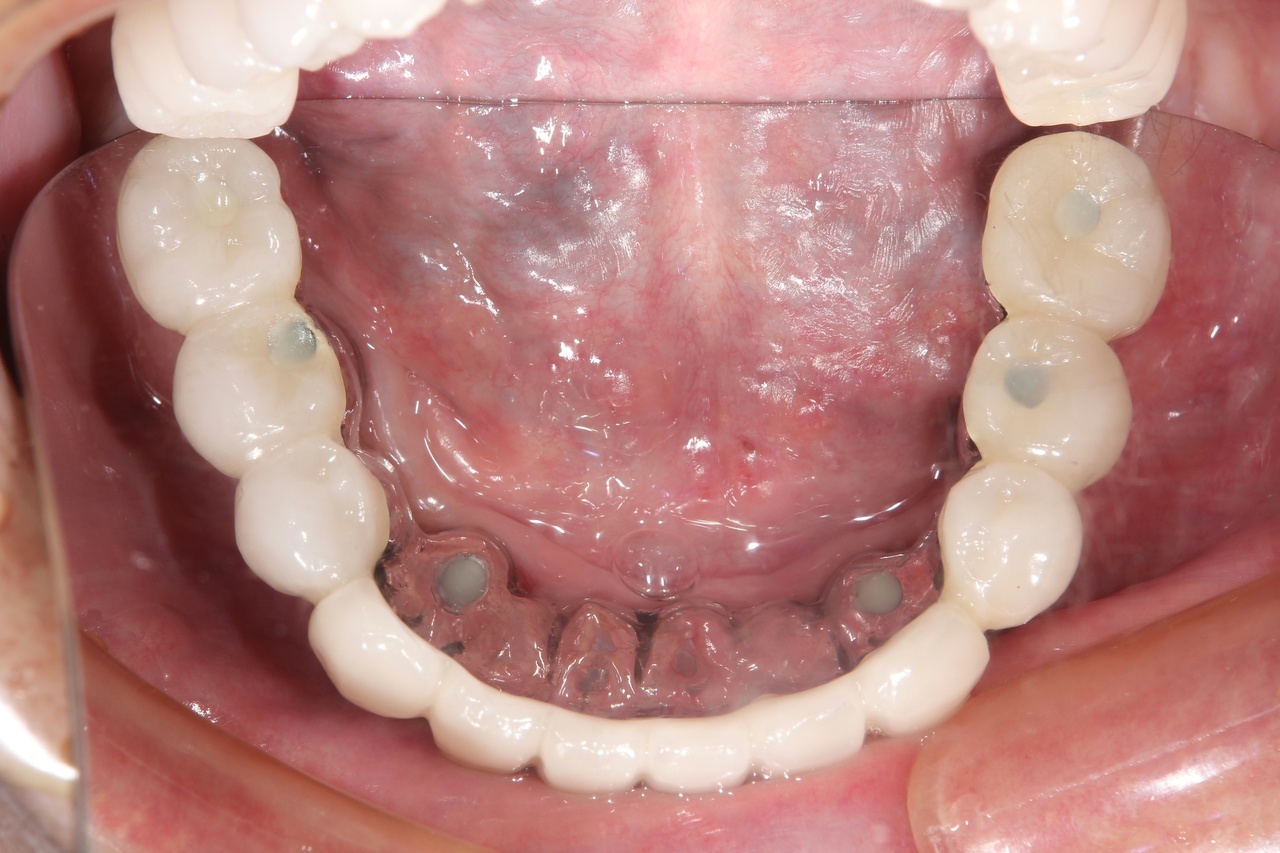

インプラントオーバーデンチャー<ロケータータイプ> (沼津市在住 男性)

インプラントを埋め込み、固定用のロケーターを装着し、入れ歯をしっかりと固定する治療法です。

少ない本数でがっちり噛める治療法です。取り外し可能でしっかり固定できるので、入れ歯の誤飲の心配がなく、手入れがしやすいので寝たきりになっても安心に使用出来ます。

しっかり噛むことで踏ん張りがきくので転んで骨折するリスク回避にもなります。

● オーバーデンチャーを外した状態

● オーバーデンチャーを付けた状態

インプラントオーバーデンチャー

インプラント4本+入れ歯:2,100,000円+税

静脈内鎮静法:0円

上顎と下顎に、インプラント4本+入れ歯、を作る場合 総額:4.200.000+税

骨の条件が良ければ、下顎の場合はインプラントの本数を減らすことができます。

【インプラント2本+入れ歯】1,550,000円+税

【インプラント3本+入れ歯】1,825,000円+税